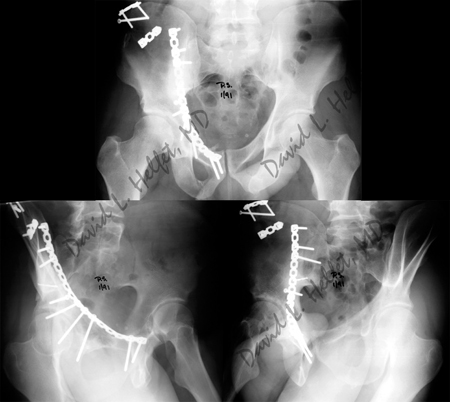

Radiographic images at two years following surgery illustrate a healed acetabular fracture

with excellent preservation of the hip joint space.